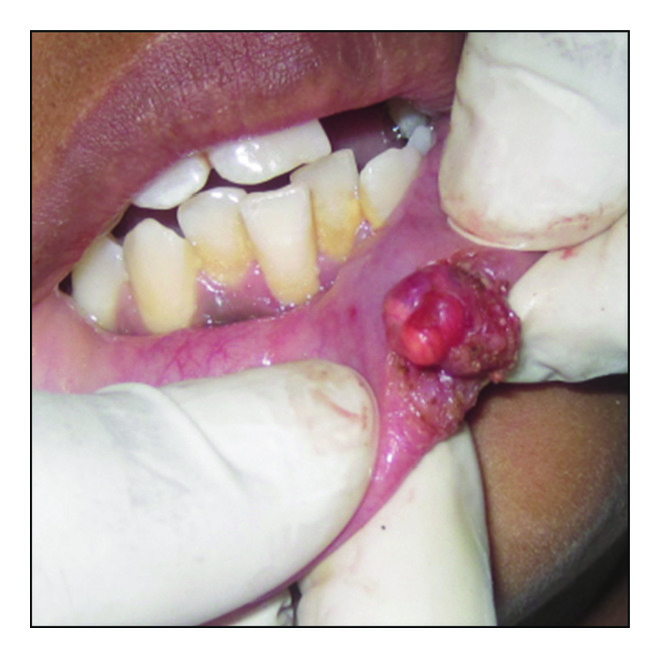

Following minimal infiltration of 1 : 2,00,000 Xylocaine, the lesion was excised using soft diode laser in wavelength of 940 nm, 400 μm diameter tip at 1.5 W in continuous mode. The incision was placed on the uppermost site of the lesion and complete excision was performed (Figures 2, 3(a), and 3(b)). The specimen (Figure 4) was subjected to histopathological examination and showed cystic cavity lined by thick fibrous capsule. Cystic lumen contains mucin, foamy macrophages, and chronic inflammatory cells. Areas of coagulation necrosis surrounding the intended biopsy material were also evident. Adjacent mucous salivary gland was also seen. With all these histopathological features, diagnosis of mucous extravasation cyst was given (Figures 5 and 6). Patient was prescribed analgesics. There was uneventful healing on 45 days of follow-up (Figures 7, 8, 9, 10, and 11).